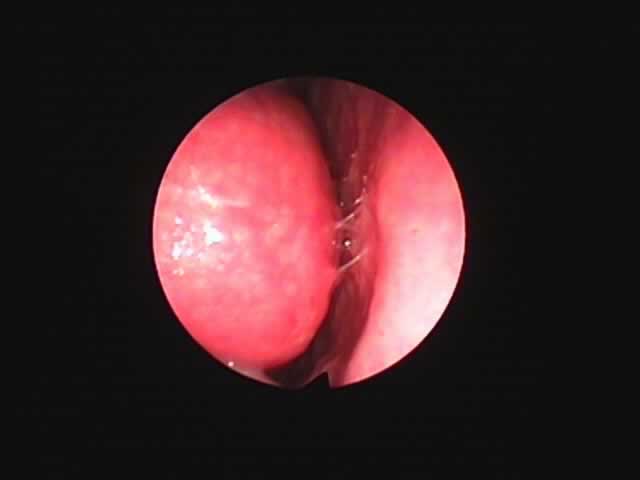

![]() |

| 左扁桃術直後(31歳男性,6月9日) 数カ所針電極を刺入 | 白い部分が変性部位(6月11日) | 右扁桃術直後(7月7日) |